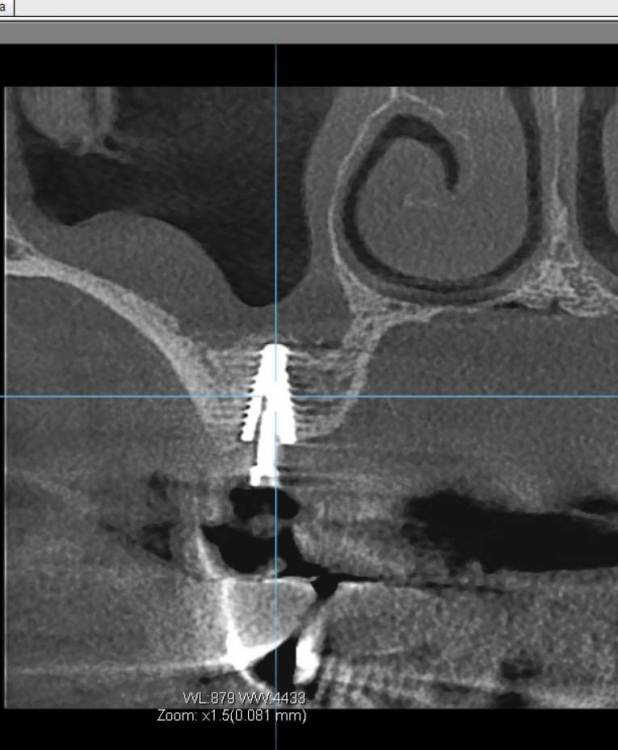

TIGER Опубликовано 22 сентября, 2022 Поделиться Опубликовано 22 сентября, 2022 (изменено) https://youtu.be/Flx36Opddh полное видео операции тут☝? Рутинный кейс)Закрытый синус,как всегда в скоп и при помощи пьезотома ,последнее фото результат через 6 месецев перед фиксацией протетики? Изменено 22 сентября, 2022 пользователем TIGER 5 1 Ссылка на комментарий

TIGER Опубликовано 7 октября, 2022 Автор Поделиться Опубликовано 7 октября, 2022 Финал 1 Ссылка на комментарий